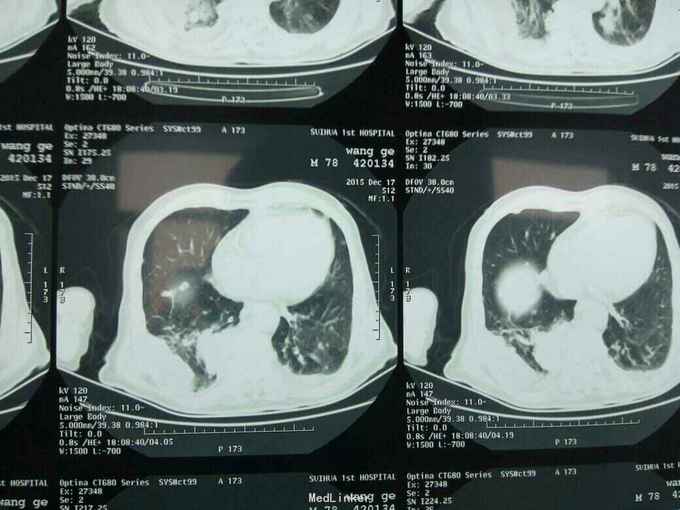

根据病史查体诊断:腰间盘突出症待确诊。应用消肿营养神经镇痛治疗。一天。查核磁共振示:腰椎多节段间盘突出伴椎管狭窄。第二腰椎骨破坏侵及椎板。部分突入椎管,脊髓受压。诊断:腰间盘突出伴椎管狭窄。第二腰椎转移癌,脊髓受压。经与家属沟通,查双肺CT:双肺下叶炎症。肺部纤维化。可见肿瘤阴影。肋骨及胸膜受累。胸椎部分骨破坏。最终诊断:双肺癌,胸椎,腰椎骨转移,脊髓受压。多节段腰椎间盘突出。病人至肿瘤科治疗。